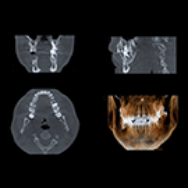

歯科用CTで

細部を詳細に把握

松友歯科クリニックでは歯科用CTを採用しています。顎の骨や神経の位置を知ることで、外科的処置が必要なインプラント治療でのリスクを抑えることが可能です。

インプラント治療を選ばれた場合は、CT検査や歯型検査を行い、顎の骨の厚みなど丁寧に確認します。また、安全な手術と快適な噛み合わせのために歯型模型を作製し、精査します。